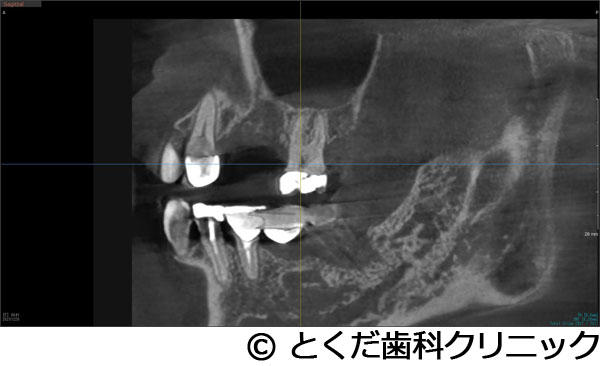

¡Ú¾ÉÎã3¡Ûº¸¾å5¤ÎËË¡¦À妤ÎÂçÉý¤Ê¹ü·ç»¤¬¤¢¤ê¡¢¤«¤Ä¡¢¾å³ÜƶÄì¤Þ¤Ç3mmÄøÅ٤δû¸¹ü¤·¤«¤Ê¤¤¾ÉÎ㤬¡¢¼£ÎÅ´ü´Ö2.5¥õ·î¤Ç¼£ÎŤ¬½ª¤ï¤Ã¤¿¥±¡¼¥¹

- º¸¾å5¤ÎËË¡¦À妤ÎÂçÉý¤Ê¹ü·ç»¤¬¤¢¤ê¡¢¤«¤Ä¡¢¾å³ÜƶÄì¤Þ¤Ç3mmÄøÅ٤δû¸¹ü¤·¤«¤Ê¤¤¾ÉÎ㤬¡¢¼£ÎÅ´ü´Ö2.5¥õ·î¤Ç¼£ÎŤ¬½ª¤ï¤Ã¤¿¥±¡¼¥¹

º¸¾å5¤Î»õº¬ÇËÀÞ¤òµ¯¤³¤·¤Æ¤¤¤¿¤¿¤á¡¢ÇÓÇ¿¤È¼«È¯Äˤòǧ¤á¤¿¡£¤½¤ì¤Ëȼ¤¦¹ü¤ÎÂ礤ʷ绡£

¼£ÎÅÊýË¡

´µ¼ÔÍͤ¬º¸¾å5¤ÎÇÓÇ¿¤ò¼çÁʤËÍ象¡¢¾Ã±ê¸å¤ËÈ´»õ¤ò´õ˾¤·¤¿¤¿¤áÈ´»õ¤ò¹Ô¤¤¤Þ¤·¤¿¡£¤½¤Î¸å¡¢´µ¼ÔÍͤ¬¥¤¥ó¥×¥é¥ó¥È¼£ÎŤò´õ˾¤·¤¿¤¿¤áÈ´»õ¸å¡¢¼þ°ÏÁÈ¿¥¤¬°ÂÄꤹ¤ë¤Î¤òÂԤäƥ¤¥ó¥×¥é¥ó¥È¼ê½Ñ¤ò¹Ô¤Ã¤Æ¤¤¤Þ¤¹¡£ÆâÍÆ¤Ï¡¢¾å³Ü´û¸¹ü¤¬Çö¤¤¤¿¤á¥°¥é¥Õ¥È¥ì¥¹¥µ¥¤¥Ê¥¹¥ê¥Õ¥È¤ÈʹԤ·¤Æ¡¢¹ü¤¬ÂçÉý¤Ë·ç»¤·¤¿Éôʬ¤Ø¤Î¹üÊäŶºÞŶÆþ¤ò¹Ô¤¤1²óË¡¤Ç¼ê½Ñ¤ò´°Î»¤·¡¢9½µ¸å¤Ë¸÷³Ø°õ¾Ý¤Ç°õ¾Ý¤ò¹Ô¤¤¡¢¥¸¥ë¥³¥Ë¥¢¤ÎºÇ½ªÊäÄÖʪ¤ò11½µ¤ÇÁõÃ夷¤Æ¼£ÎŤò´°Î»¤·¤Æ¤¤¤Þ¤¹¡£